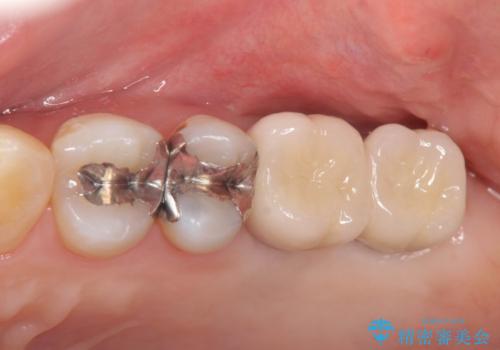

上顎奥歯のインプラント治療

- 奥歯を失い咬合機能の回復のためインプラント治療を希望され来院されました。

奥歯を2本失うと、他の歯の負担が増加し残っている歯の状態が悪くなるリスクがあります。

しっかりと咬合機能の回復できるインプラント治療を計画します。

しっかりと食事ができるようになり、当院のインプラント治療に満足いただくことができました。